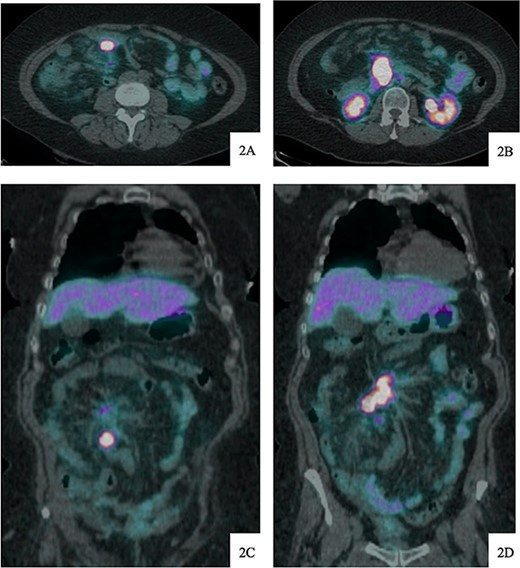

DOTATATE positron emission tomography-computed tomography scan at time of diagnosis in November 2017 revealed a small bowel primary tumor in the right lower quadrant consistent with terminal ileum (A) as well as the periduodenal mass near the root of the mesentery (B). Coronal reformatting redemonstrates the primary tumor (C) and mesenteric mass (D).

DOTATATE positron emission tomography-computed tomography scan revealing extent of metastatic disease.